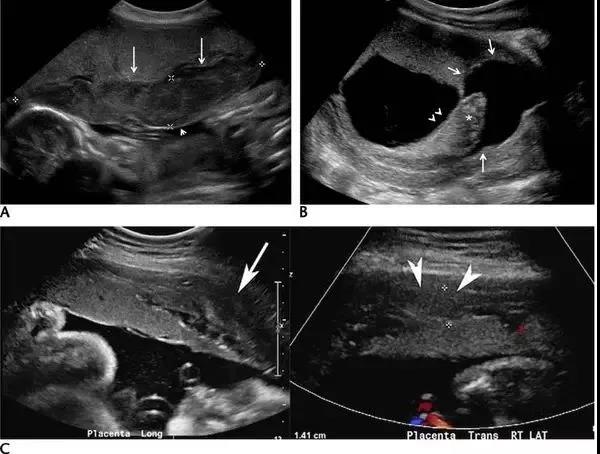

胎盘早剥的超声诊断:A 为孕 24 周时的胎盘横切面,胎盘表面(长箭头)与羊膜(短箭头)之间可见一个较大的低回声区,此为胎盘前早剥。B 为孕 11 周的子宫矢状面,可见胎盘后的慢性无回声出血灶(长箭头),并延伸至绒毛下空间(短箭头),星号示出血灶导致胎盘边缘抬起。C 为另一孕 27 周伴无痛性阴道出血患者的子宫矢状面及横切面,长、短箭头所指回声为胎盘后的亚急性出血灶。

胎盘早剥(placental abruption)是指妊娠20周后或分娩期,正常位置的胎盘在胎儿娩出前,部分或全部从子宫壁剥离,发病率为0.4%~1.0%。